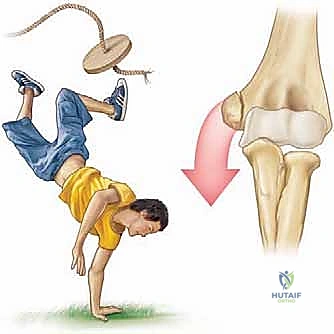

Medial epicondyle fractures represent approximately 11% to 20% of all pediatric elbow fractures, with a peak incidence occurring between the ages of 9 and 14 years. This demographic distribution corresponds directly to the vulnerability of the medial epicondylar apophysis prior to its final radiographic fusion, which typically occurs between 15 and 18 years of age. The pathophysiology of this injury is almost exclusively driven by an indirect, avulsion-type mechanism. During a fall on an outstretched hand (FOOSH) with the elbow in terminal extension, a massive valgus moment is generated. This force translates into extreme tensile stress across the medial structures. The robust flexor-pronator muscle mass and the anterior bundle of the ulnar collateral ligament (UCL) subsequently avulse the weaker apophyseal growth plate.

Direct trauma to the medial aspect of the elbow is a distinctly rare cause of this fracture pattern. Far more commonly, these fractures are intimately associated with an acute elbow dislocation, occurring in up to 50% of displaced medial epicondyle fractures. It is imperative to understand that the elbow may spontaneously reduce prior to the patient's arrival at the emergency department. Consequently, a high index of suspicion for a transient dislocation event must be maintained, as this implies a more extensive soft-tissue injury, including disruption of the lateral collateral ligamentous complex and the anterior capsule.

The flexor-pronator mass originates from the anterior and inferior aspects of the medial epicondyle. This robust muscle group comprises the pronator teres, flexor carpi radialis, palmaris longus, flexor digitorum superficialis, and flexor carpi ulnaris. When the apophysis is avulsed, the resting tone and active contraction of these muscles displace the fragment distally, anteriorly, and often internally rotate it. The UCL, specifically its anterior bundle, is the primary restraint to valgus stress at the elbow, providing over 50% of the valgus stability from 20 to 120 degrees of flexion. The anterior bundle originates from the anteroinferior surface of the medial epicondyle and inserts onto the sublime tubercle of the proximal ulna. Because the UCL remains attached to the avulsed epicondylar fragment, the fracture inherently represents a functional UCL rupture. Restoring the bony anatomy is therefore synonymous with restoring the ligamentous stability of the joint.